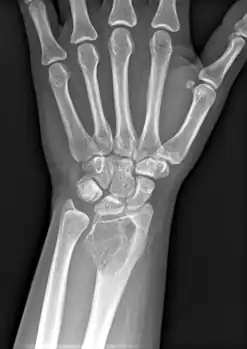

Front view X-ray. A well-defined expansile lesion in radius near wrist

On X-ray, giant-cell tumors (GCTs) are lytic/lucent lesions that have an epiphyseal location and grow to the articular surface of the involved bone.[11] Radiologically the tumors may show characteristic 'soap bubble' appearance.[12] They are distinguishable from other bony tumors in that GCTs usually have a nonsclerotic and sharply defined border. About 5% of giant-cell tumors metastasize, usually to a lung, which may be benign metastasis,[13] when the diagnosis of giant-cell tumor is suspected, a chest X-ray or computed tomography may be needed. MRI can be used to assess intramedullary and soft tissue extension.